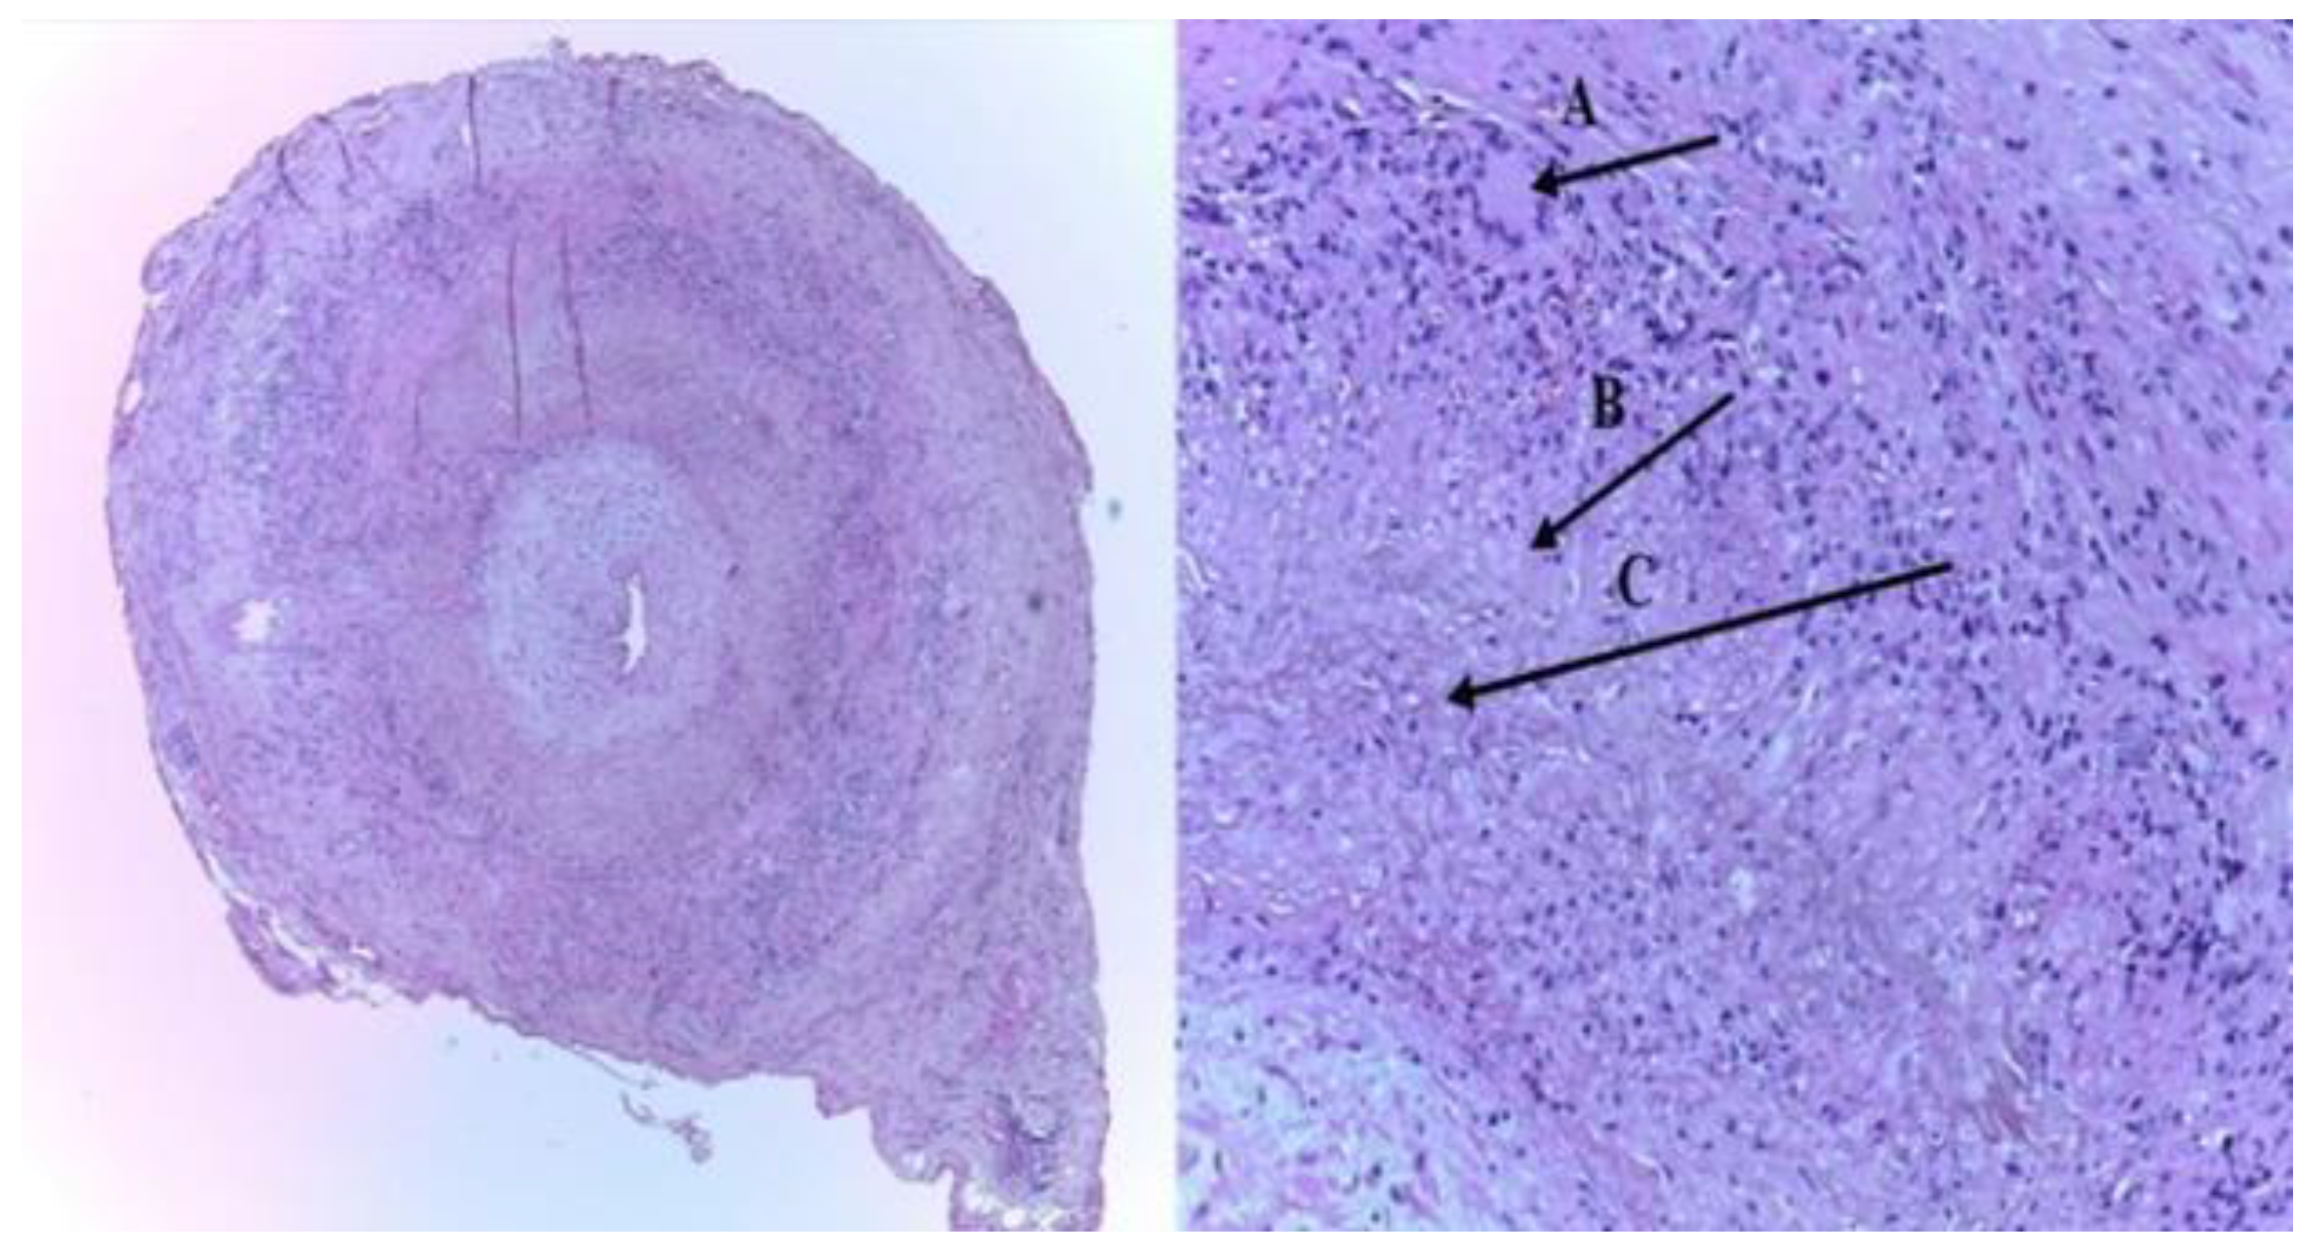

A temporal artery biopsy (TAB) sample, indicating necrotizing of the vessel wall, with predominant mononuclear cell infiltrates or a granulomatous pathological process represented by multinucleated giant cells

[7][8] (

Figure 1)

[9].

Figure 1. The histopathologic picture of the left superficial temporal artery biopsy (TAB): (A) intimal thickening, and an inflammatory infiltrate with giant cells of the media layer (typical granulomatous inflammation), (B) epithelioid cells, and (C) characteristic internal limiting lamina fragmentation (H&E staining-left-×40; right-×100)